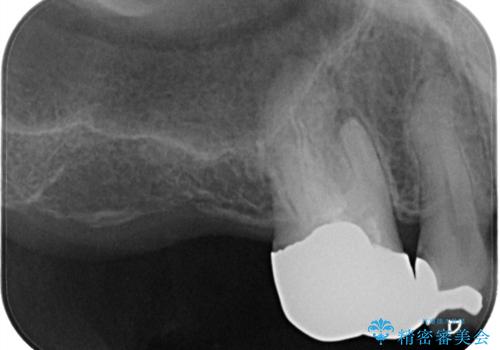

- 患者様は、右側の奥歯でしっかり噛めないことを主訴に来院されました。診察の結果、右上6・右下6の根管治療が不十分で、感染のリスクがある状態と判断。これらの歯は再根管治療を行い、セラミッククラウンで補綴することにしました。また、右上7・右下7は欠損しており、噛み合わせを回復するためにインプラント治療を計画しました。

まず、右上6・右下6の根管治療を再度行い、根の状態をしっかり整えた上で、セラミッククラウンを装着しました。さらに、欠損していた右上7・右下7にはインプラントを埋入し、セラミッククラウンを装着。治療後は、「奥歯でしっかり噛めるようになり、不安なく食事ができるようになった」と患者様にも大変ご満足いただきました。